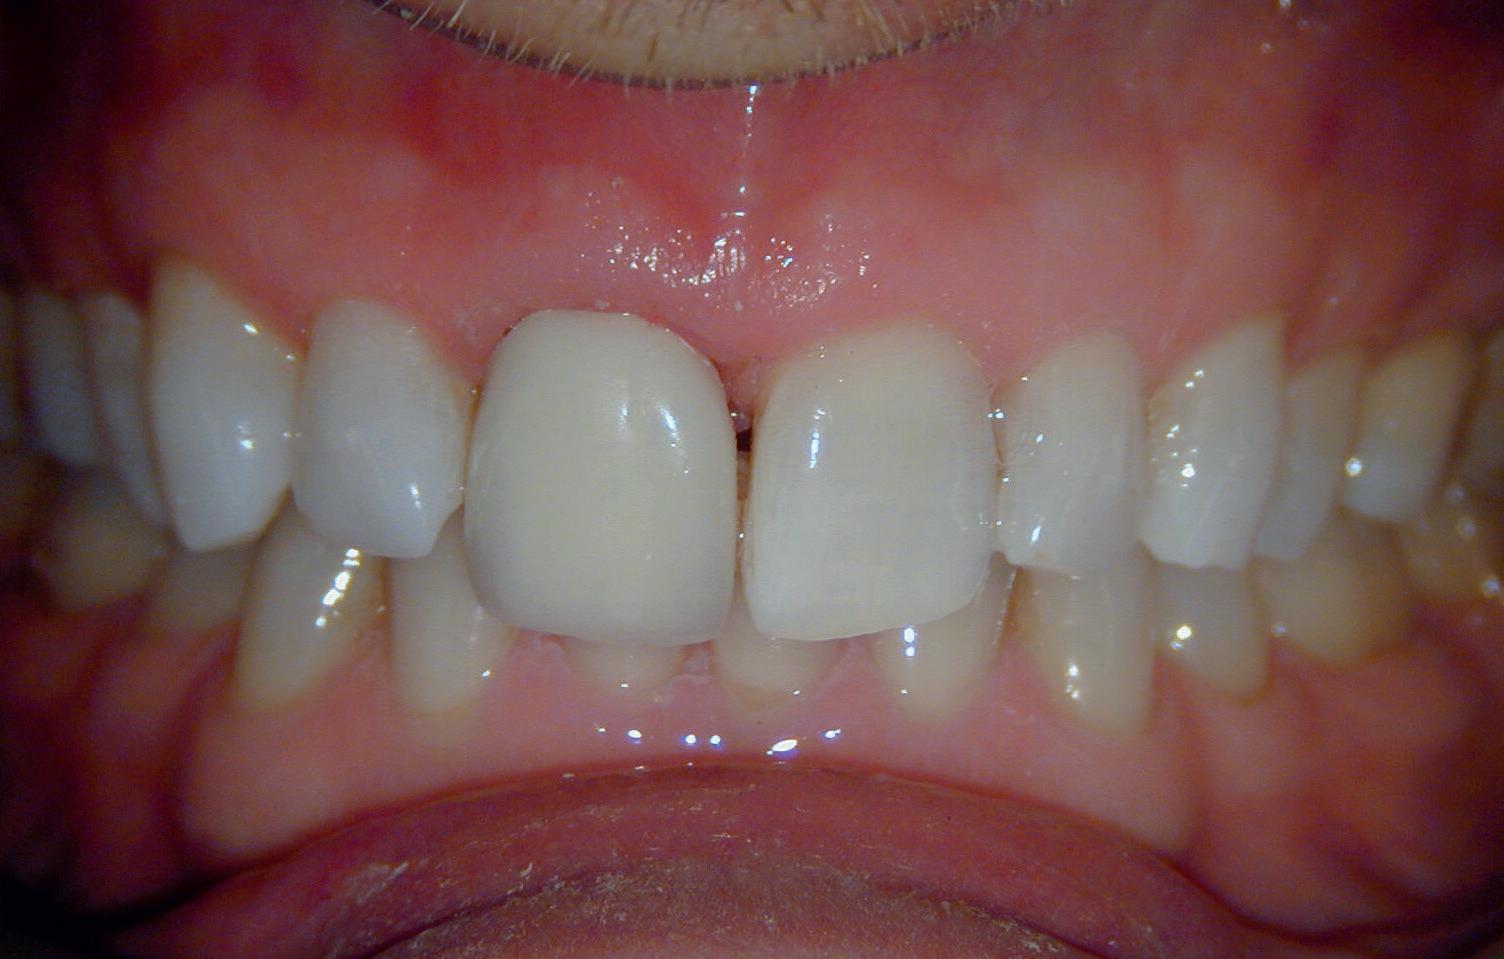

13. Techniekmodel

plaatsing van de restauraties werden zowel de tandboog als de tandstand in de bovenkaak gecorrigeerd (afbeelding 13-15).

Aansluitend werd de onderkaak volgens hetzelfde principe gerehabiliteerd, resulterend in een stabiele, functionele en esthetisch gebalanceerde occlusie (afbeelding 16-17).